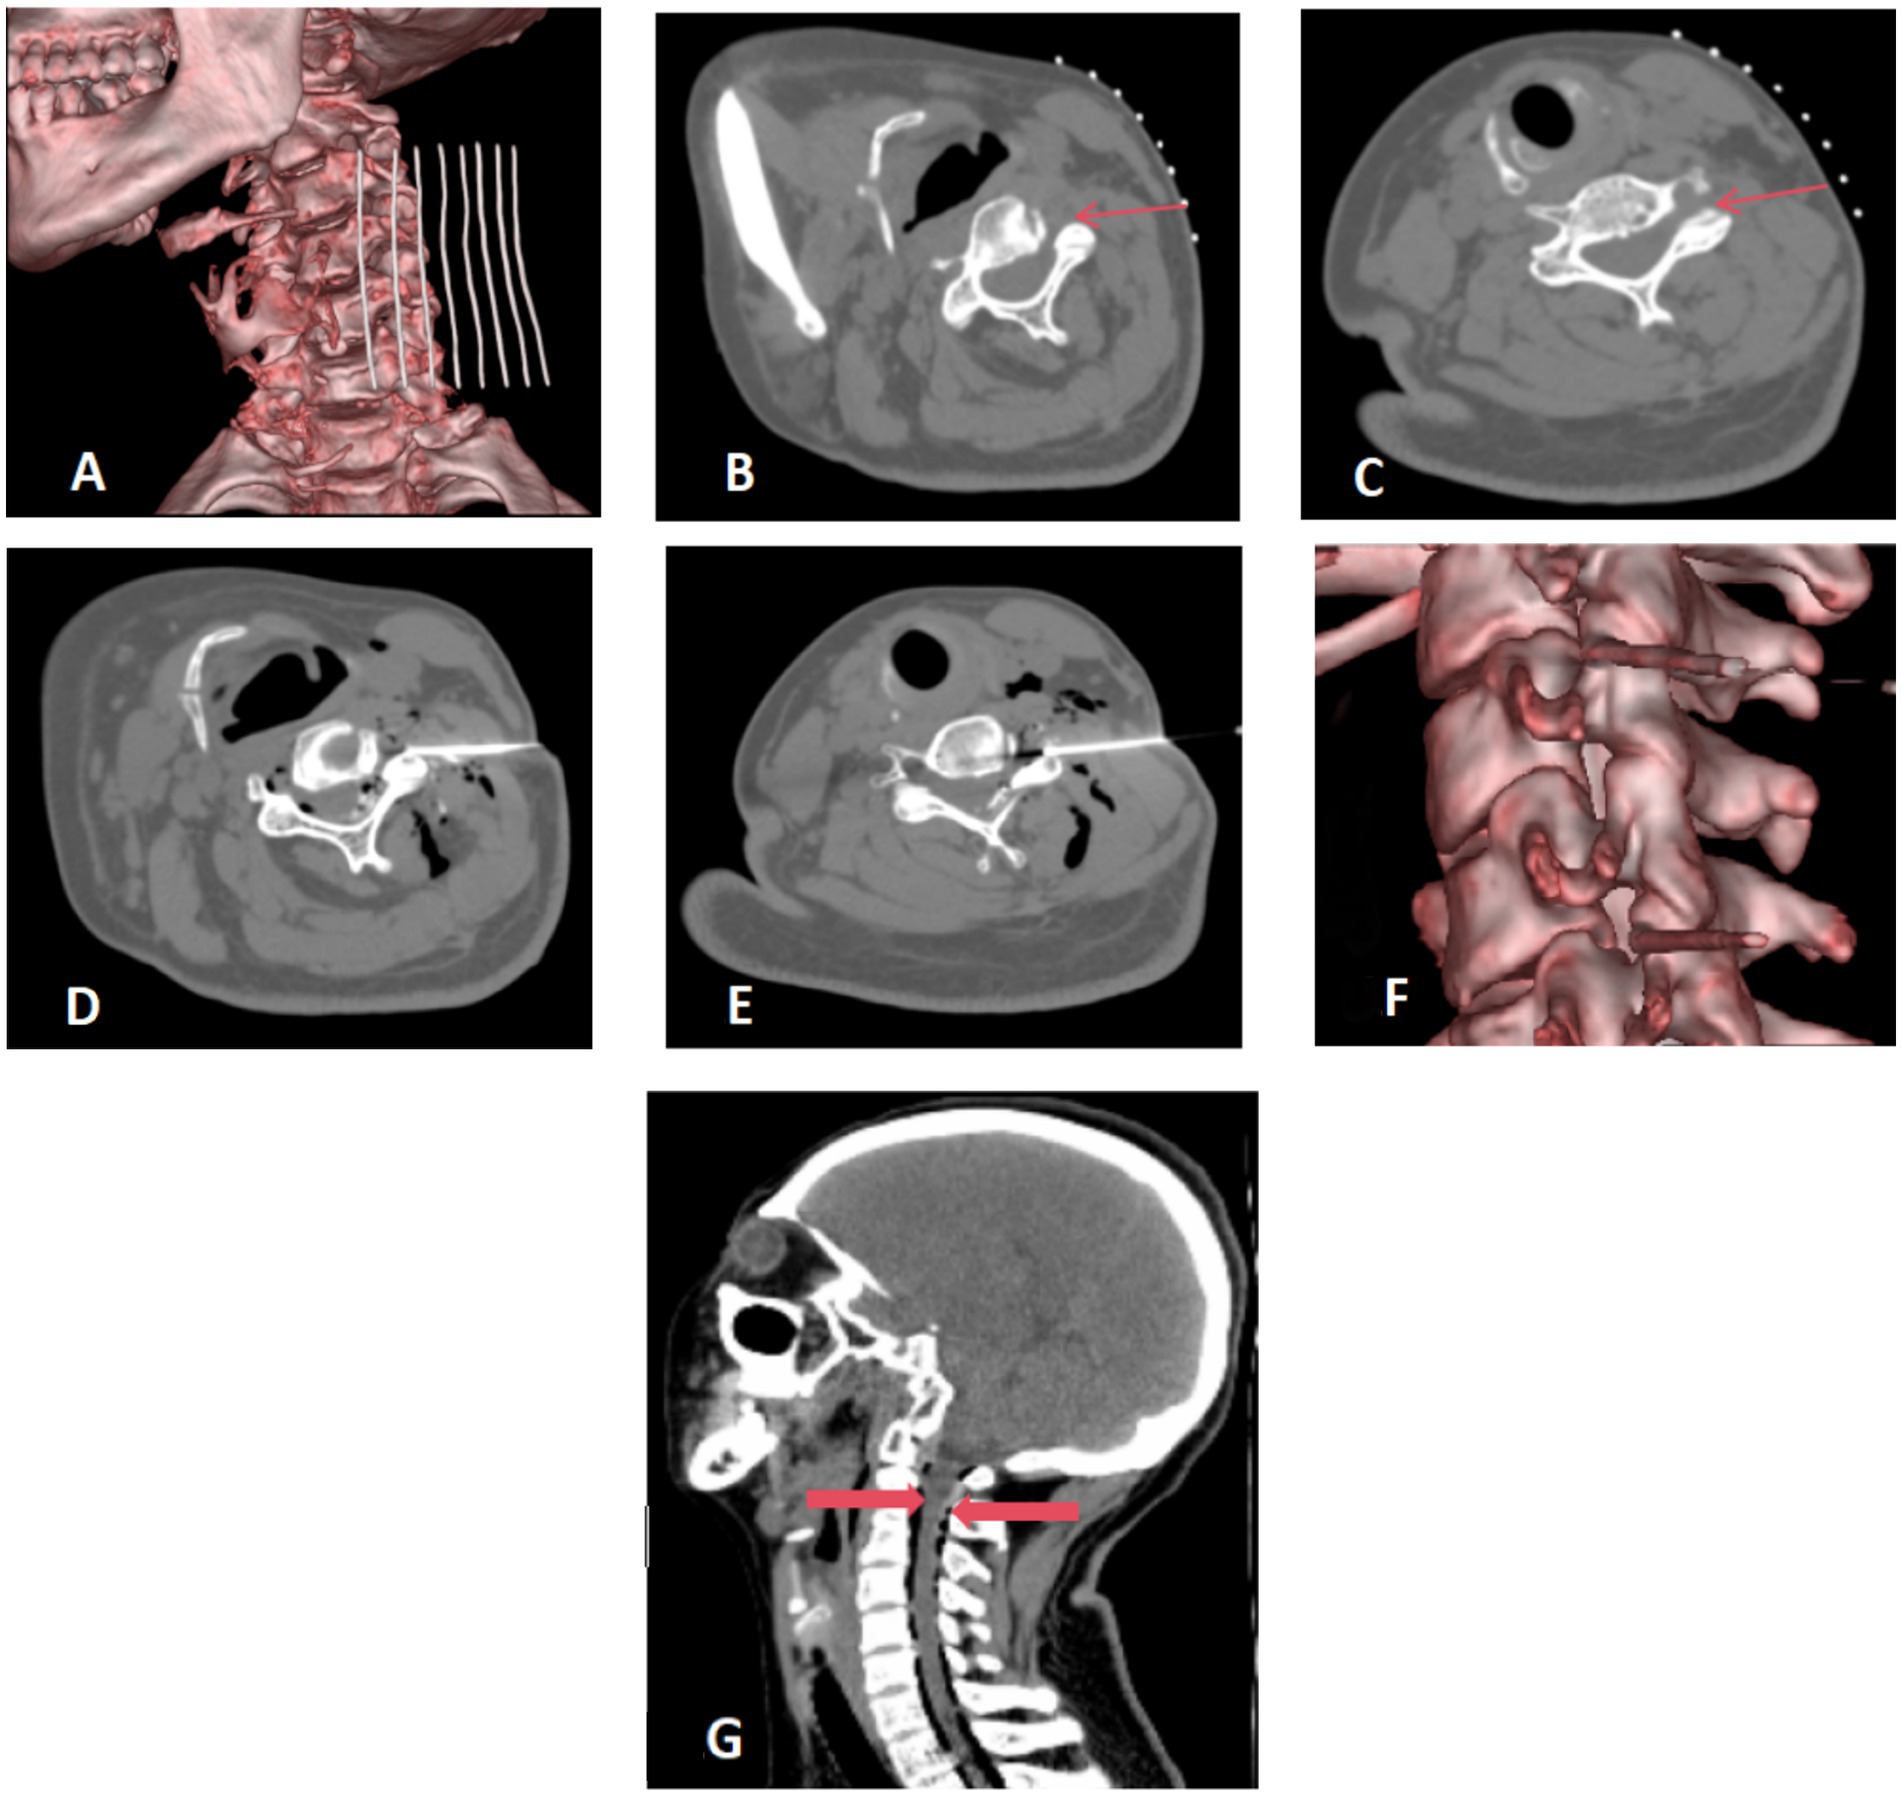

Patients were positioned supine on the CT examination table, with their heads turned toward the unaffected side. A custom-made metal fence was attached to the upper neck area. A detailed CT scan of the neck was performed with a slice thickness of 1.0 mm, effectively mapping the area for surgical intervention (Figure 1A). Using the anterolateral cervical approach, the physician accurately located the unilateral intervertebral foramen at the C3/4 and C5/6 level. The puncture path and angle were meticulously set (Figures 1B,C).

Medical imaging series showing cervical spine evaluations. Image A: 3D reconstruction of the cervical spine. Images B to E: CT scans with cross-sectional views showing detailed anatomy and marked areas. Image F: 3D detail of vertebrae. Image G: Sagittal CT scan of the head and neck highlighting vertebrae with red markers.

Figure 1. (A–C) Preoperative positioning: the patient was positioned supine on the operating table, with the head turned towards the contralateral side. A metal grid marker was strategically placed on the neck to facilitate precise targeting. The cervical anterolateral approach was employed, focusing on the articular pillar surfaces at the C3/4 and C5/6 levels. These target areas were distinctly marked with fine red arrows for clear visualization. (D–F) Needle placement and injection. The needle was precisely inserted along a pre-established pathway targeting the surface of the superior articular process. A therapeutic mixture consisting of 10 mL of ozone blended with physiological saline, complemented by 1 mL of contrast agent, was meticulously injected at each designated site. Virtual Reality (VR) reconstruction techniques were utilized to confirm the accurate positioning of the needle tip at the level of the intervertebral foramen. (G) Postoperative CT scan reconstruction. The sagittal view of the cervical spine after surgery exhibits a satisfactory dispersion of ozone throughout the spinal canal. Gas shadows, clearly surrounding the dura mater, are marked by thick red arrows. There are no indications of hemorrhage detected in the visualized areas.

Following routine disinfection and draping, local anesthesia was administered using 1% lidocaine. A 14 cm long coaxial trocar with a Hakko 22G needle was inserted, directed to the upper process surface (illustrated in Figures 1D,E), with the needle tip positioned within the foramen (Figure 1F).

The core of the trocar was removed to inject 10 mL of ozone mixed with 10 mL of saline and 1 mL of iodoxanol. This allowed for visualization of the contrast distribution within the spinal canal and around the spinal nerve roots (Figure 1F). A subsequent CT scan was performed post-procedure to confirm the optimal spread of the ozone and contrast agent within the cervical spinal canal, and to check for any presence of bleeding (Figure 1G).